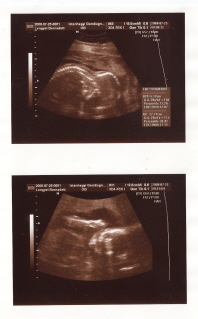

Ma reggel apus érezte a tenyerével Íriszke mozgását,könnybe lábadt a szeme,aztán hirtelen ki kellett mennie rögtön a kutyának enni adni,pedig szerintem már előtte adott neki...

Arany szive,milyen érdekes pedig már a 3dikat várjuk mégis milyen megható újra-és újra átélni ezeket a dolgokat.

Csak zöldinek az eddigi fázisok: